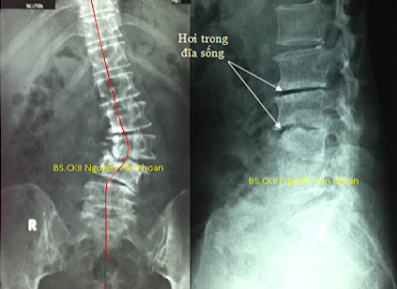

- Vẹo cột sống do thoái hóa (degenerative scoliosis): Các loại vẹo cột sống khác chỉ gặp ở trẻ nhỏ và tuổi teen (dưới 20 tuổi), vẹo cột sống do thoái hóa chỉ xảy ra ở người lớn tuổi do biến đổi thoái hóa. Do sự suy yếu của hệ thống dây chằng và các cấu trúc mô mềm khác quanh cột sống, kết hợp với sự tạo các gai xương bất thường gây nên sự cong vẹo bất thường của cột sống. Vẹo cột sống thoái hóa cũng có thể do loãng xương, gãy lún đốt sống hoặc do thoái hóa đĩa đệm.

Thường gây đau lưng và chân do có liên quan đến bệnh Viêm khớp ở cột sống, chèn ép rễ thần kinh gây đau lan xuống chân. Điều trị bảo tồn gồm vật lý trị liệu, tập vận động, xoa bóp nắn chỉnh nhẹ nhàng cũng có thể giúp giảm đau. Nếu bệnh không cải thiện với các biện pháp trên thì có thể mổ. Cần chụp X-quang và cộng hưởng từ (MRI) cột sống để lên kế hoạch mổ. Mổ có thể chỉ giải ép thần kinh, cắt bỏ các gai xương chèn ép thần kinh. Một số trường hợp cần nắn chỉnh vẹo, cố định bằng dụng cụ và hàn xương.